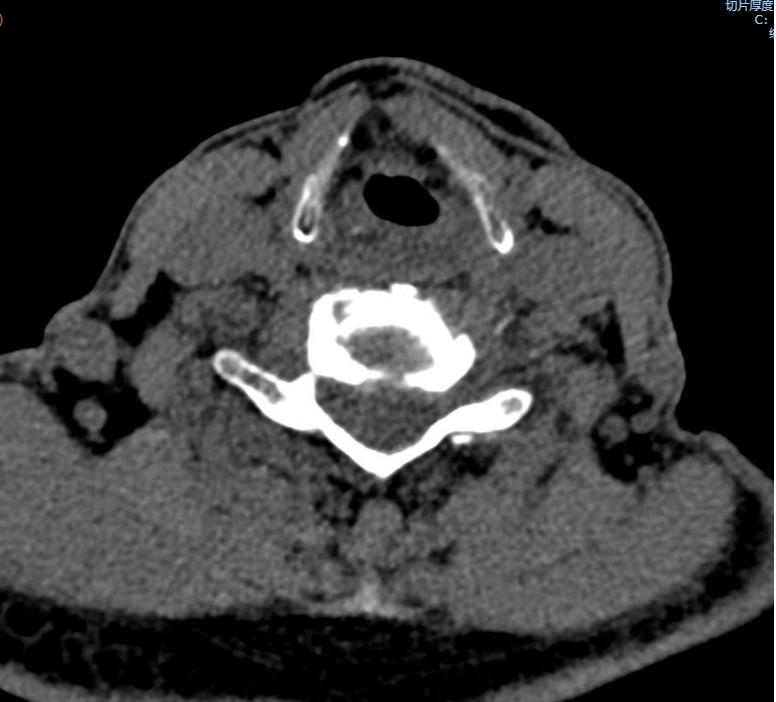

手術之后3天,黃大伯疼痛得到很好緩解,露出了許久沒有的笑容,終于可以安心躺著睡覺了,1個月后基本恢復了正常生活,6個月后復查CT發(fā)現(xiàn)突出的頸椎間盤已經(jīng)基本消失了,黃大伯一家人對治療效果非常滿意。

手術之前CT,巨大突出物 術后6個月復查CT:突出物消失